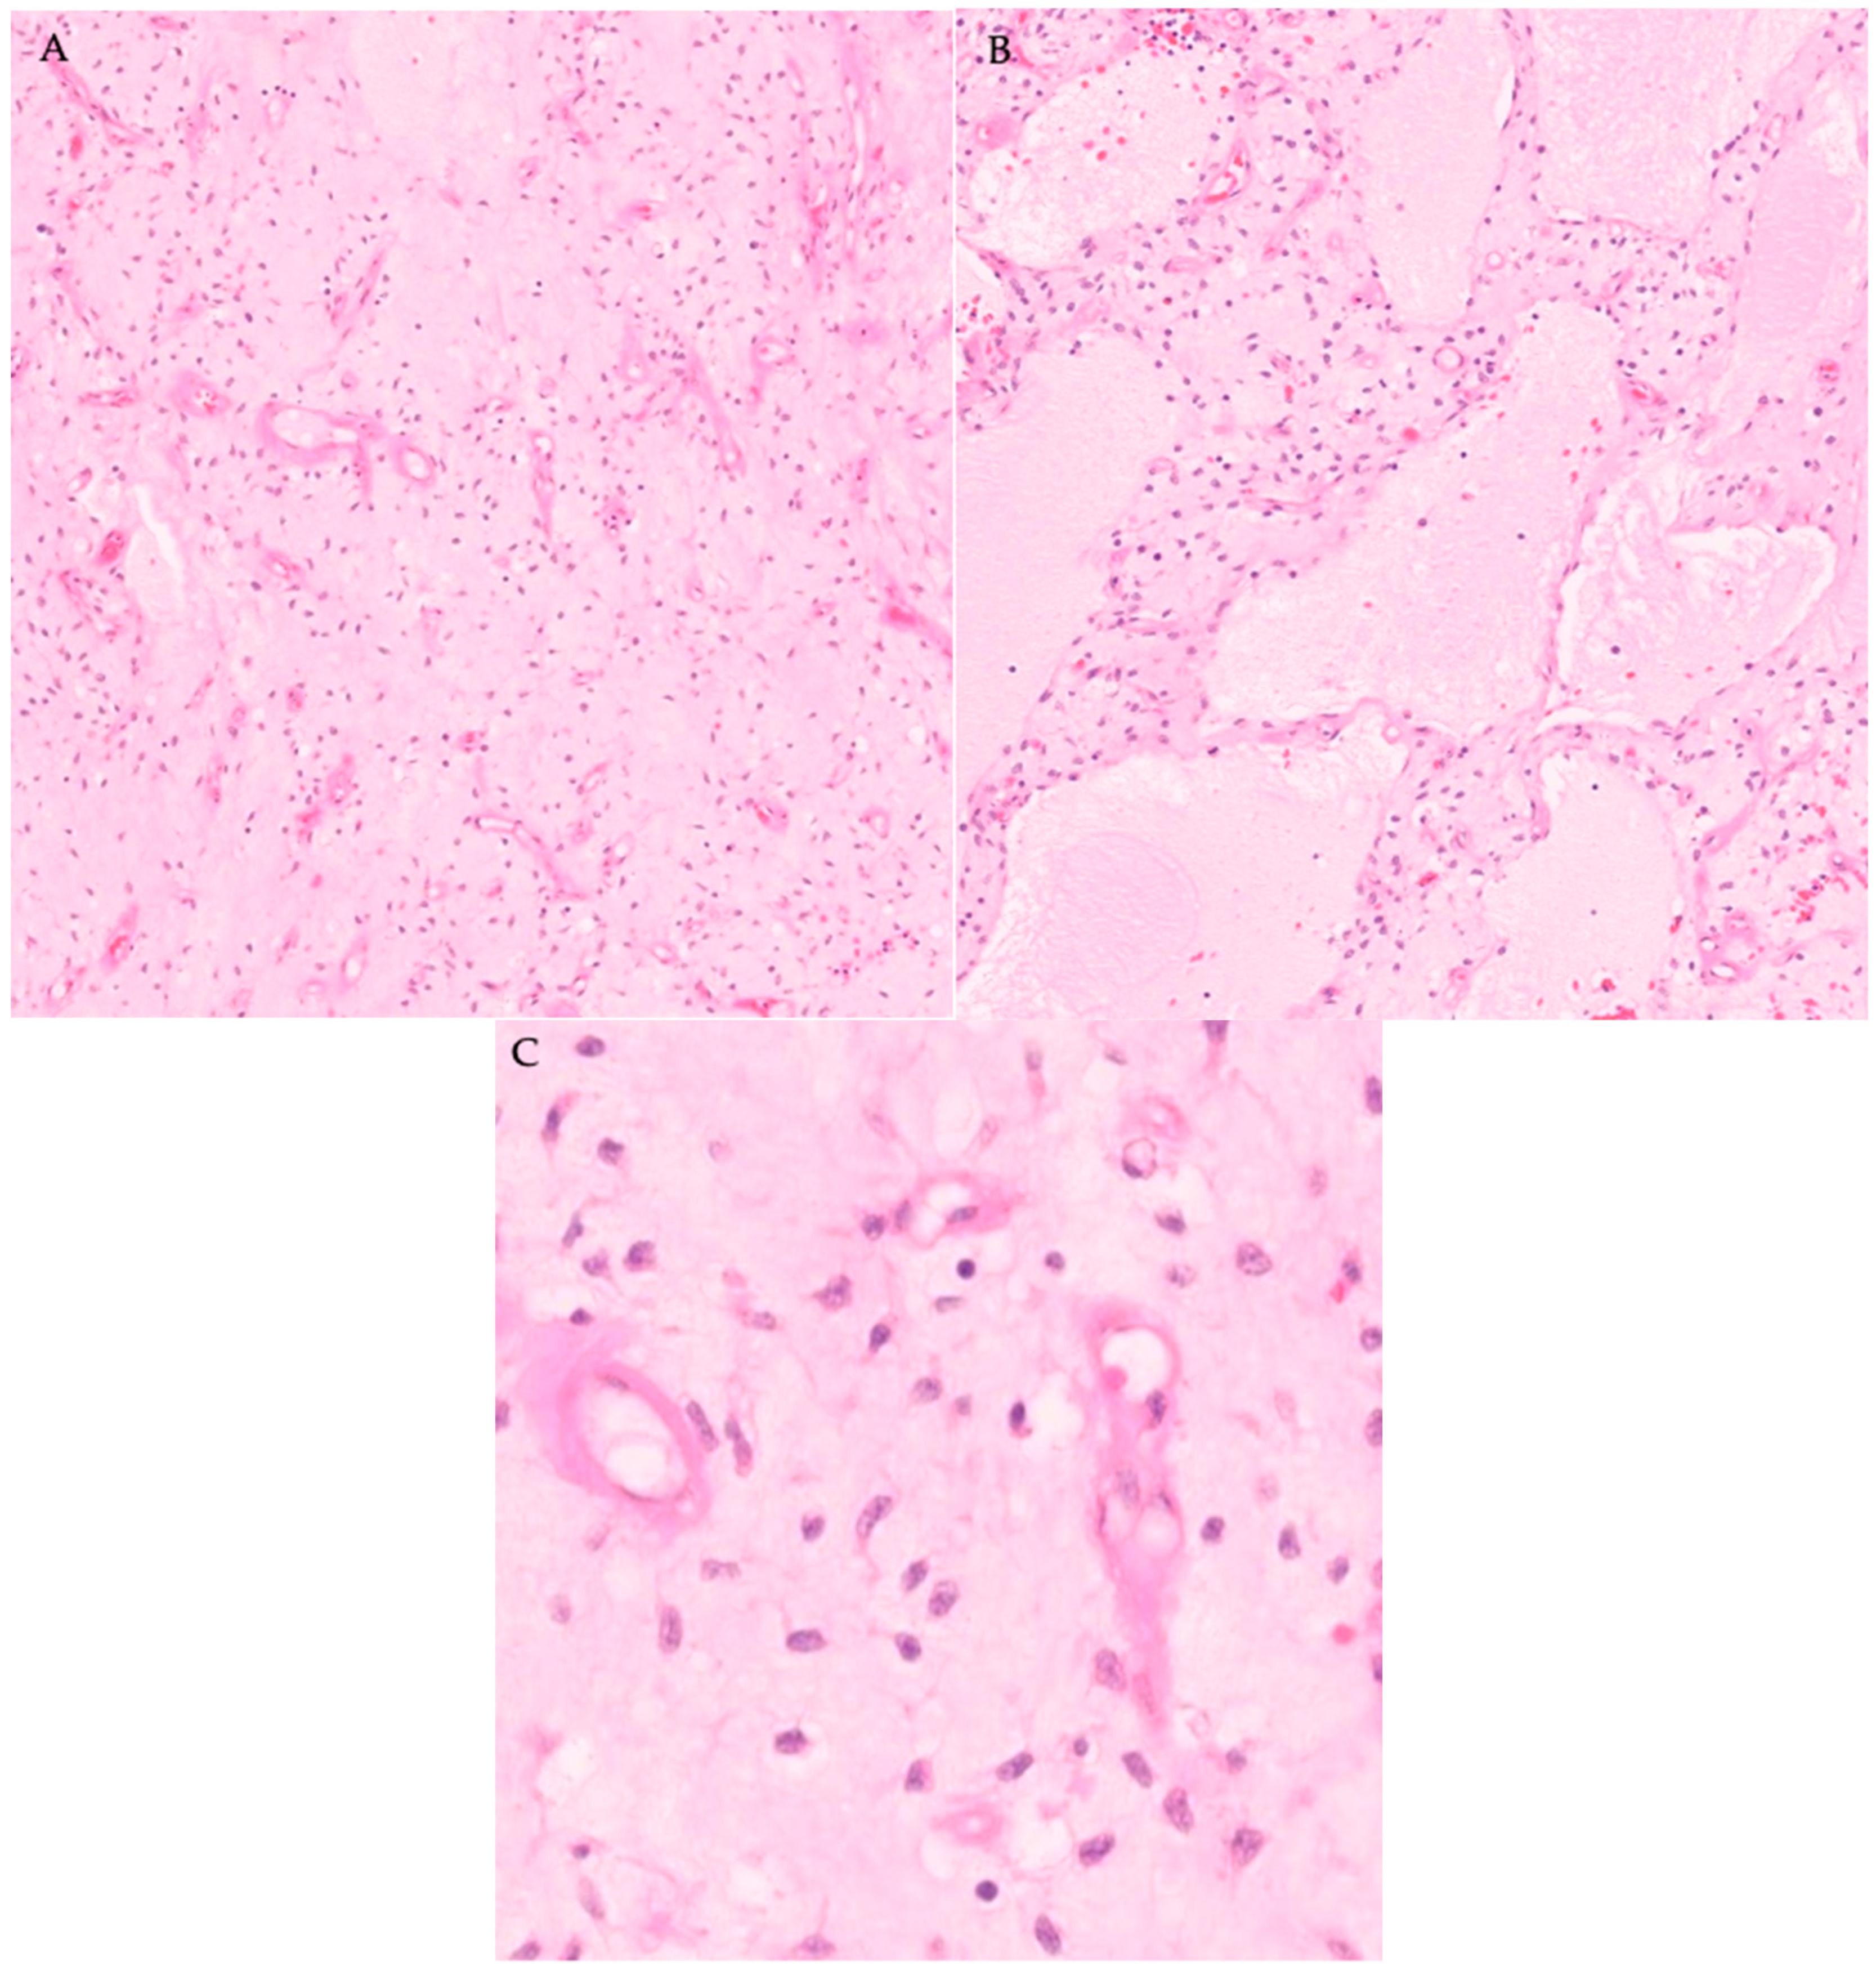

The mass was also sent for pathological evaluation to a tertiary center, and the final pathology report confirmed the diagnosis of a MLPS FNCLCC grade 2 (intermediate grade). The mass was found to have a fibrous pseudocapsule approximately 0.1 cm in thickness that was not considered an adequate margin although the inked surgical margins are negative. The surrounding tissue were normal and free of any microscopic tumor invasion. Neoplastic spindle shaped cells comprising the tumor were embedded within myxoid stroma with a background plexiform vascular network. There was no evidence of nuclear pleomorphism, increased mitotic activity, or necrosis (Figure 4). A round cell component was not identified. Immunohistochemical staining showed that the tumor cells were positive for DDIT3, and fluorescence in situ hybridization (FISH) revealed a rearrangement of the DDIT3 gene, further supporting the diagnosis of MLPS. According to the AJCC 8th Edition staging system for soft tissue sarcoma of the extremity, the tumor was staged as cT3N0M0, corresponding to Stage IIIA disease, based on tumor size and intermediate histologic grade.

Figure 4. (AC): Moderately cellular and composed of uniform spindle and stellate cells with dark staining oval nuclei and amphophilic cytoplasm enmeshed in a prominent myxoid stroma that contains a plexiform supportive vascular tree. There are infrequent lipoblasts and adipocytes throughout the mass. (A) 10× (B) 10× (C) 40×.